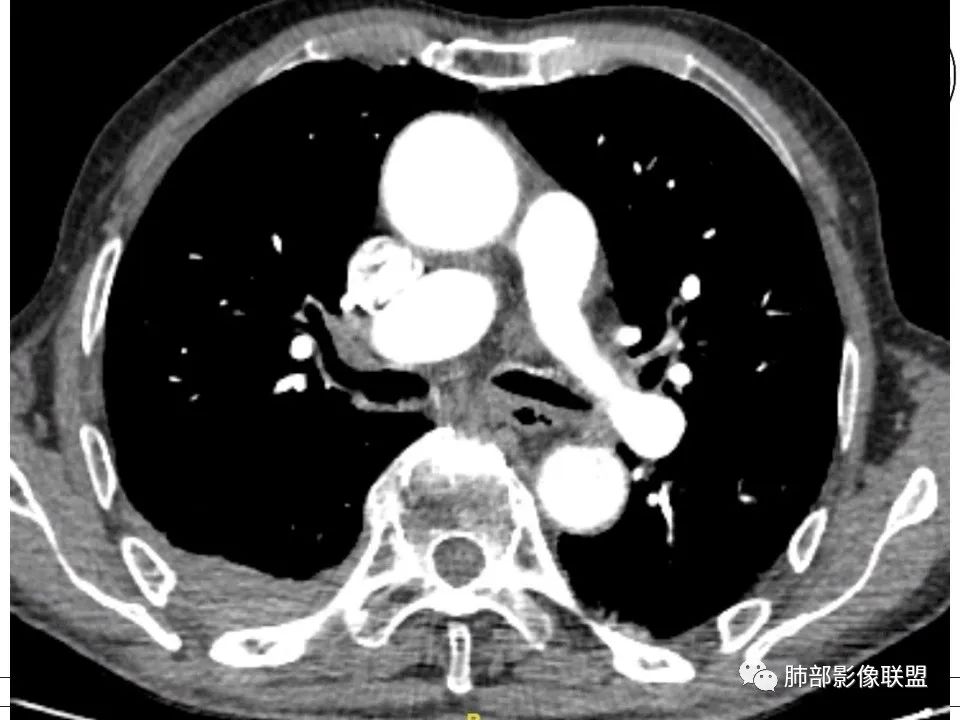

1、老年男性,右侧后胸壁软组织肿块延伸范围较广(至后纵隔主动脉旁),平扫密度均匀稍高,增强扫描均匀强化,其间走行肋间动脉包埋、漂浮(夹心三明治),部分包绕肋骨,肋骨骨质未见明显吸收破坏!

2、胸膜掀起或尾征,胸壁肋间肌及脂肪间隙浸润,肋间动脉供血。

3、纵隔淋巴结多发肿大,部分有融合。 医学百科网 | YxBaike.Com

4、双侧未见典型胸膜斑,提示石棉非长期接触。胸膜病变不广泛。淋巴结改变与胸膜病灶不相称。